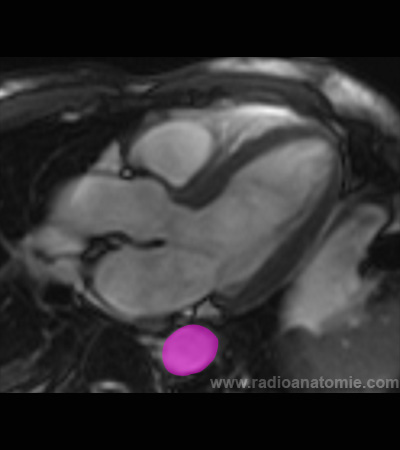

Radioanatomie et plans de coupe en IRM cardiaque

Ventricule droit